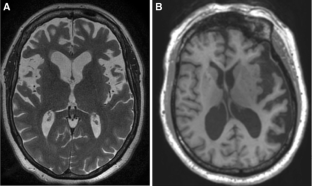

Fig. 1